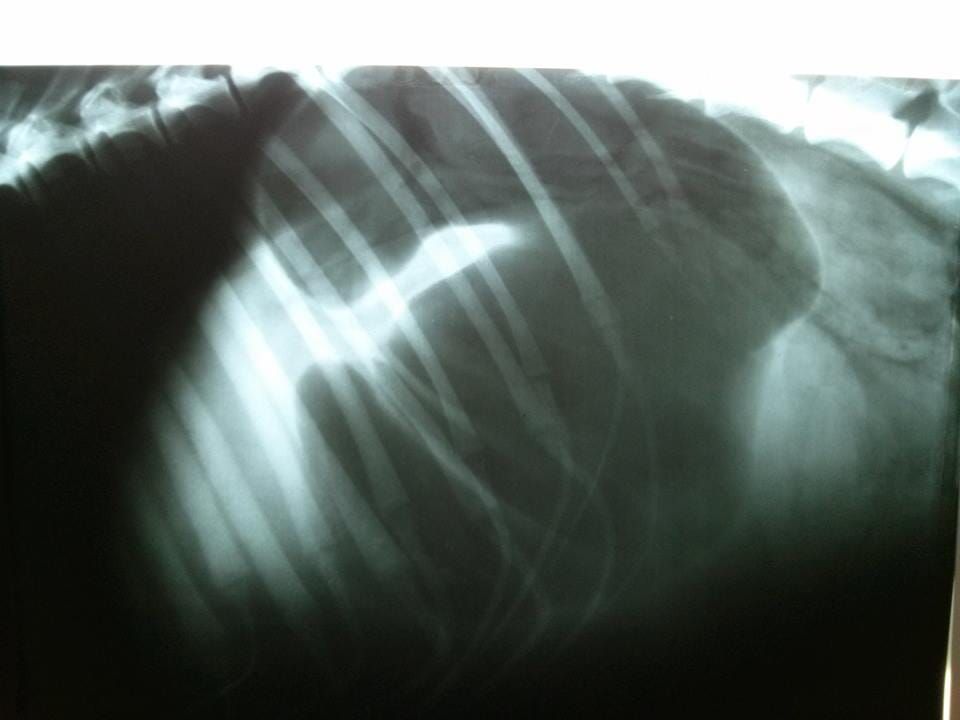

Ογκολογικές παθήσεις (Λέμφωμα, Μαστοκύτωμα, Λευχαιμίες, νεοπλάσματα κοιλίας / θώρακα)

Παθήσεις Αναπνευστικού Συστήματος (παθήσεις τραχείας, βρογχοπνευμονοπάθειες, πλευριτική συλλογή κ.α.)